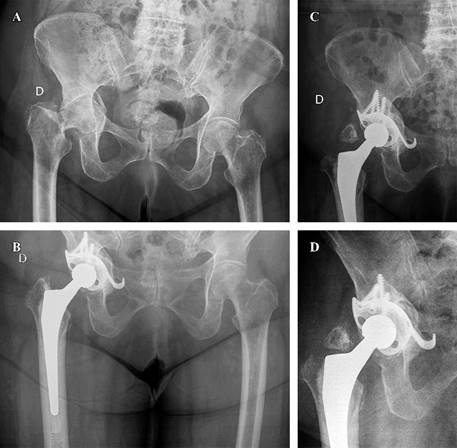

En cuanto al tipo de implante utilizado, en cinco casos se realizó reconstrucción con el concepto «CAGECUP» con una copa de tantalio multihole que permite fijar en múltiples direcciones, media de 56 mm (52-62), fijación con cuatro tornillos (3-5) con cabeza de 36 mm (Figura 1). Las otras dos fracturas requirieron de un implante de reconstrucción tipo anillo de Burch-Schneider (inserto 44 mm, cabeza 28 mm) por elección del cirujano principal debido a que eran fracturas con mayor inestabilidad, un caso de ambas columnas y en una de columna anterior y hemitransversa posterior por el desplazamiento ocurrido entre fragmentos (Figura 2). En todos los casos se utilizó autoinjerto de cabeza de fémur, en uno de los cuales se asoció además a sustituto óseo DBX® (Depuy Synthes) más chips de esponjosa por considerarse autoinjerto cuantitativamente insuficiente. Se implantó vástago cementado en cuatro casos y no cementado en tres (Tabla 2).

Figura 2: Mujer de 73 años con fractura de trocánter mayor y cuello femoral, asociada a una fractura de columna anterior y hemitransversa posterior. Se manejó con una reconstrucción tipo anillo de Burch-Schneider. A) Se observa la fractura inicial (fractura de cotilo con fractura de cuello femoral). B) Radiografía de control postoperatorio. C) Imagen radiológica al segundo año; revela una fractura desplazada del trocánter mayor tras una caída. D) Radiografía de control a los 10 años postoperatorios; muestra una adecuada integración sin complicaciones.